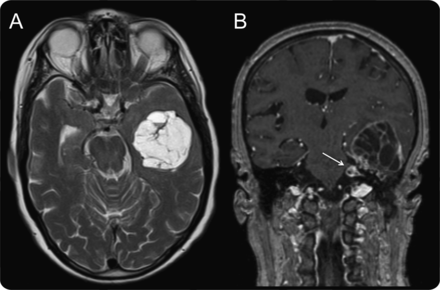

面部神经是第三个最频繁的颅内神经鞘瘤的位置,面部麻痹性痴呆最常见的标志。1,2一个77岁的女人面对失忆;细微精神状态检查得分是26日正常颅神经功能。一个巨大但第七神经神经鞘瘤被确认在左边中间窝,组件颞骨肿瘤的面神经管,膝状神经节和内部听觉运河(图)。海马体的压缩可能占临床表现。中间窝肿瘤切除的组件质量效应,与医源性面部麻痹。

面部神经鞘瘤的MRI

(A) Extra-axial质量位于左边中间窝但外观。定义良好的极限压缩相邻脑实质的损伤,没有周围的水肿。(B)有更多的参与内部听觉运河入侵左边pontocerebellar水箱(箭头所指)。